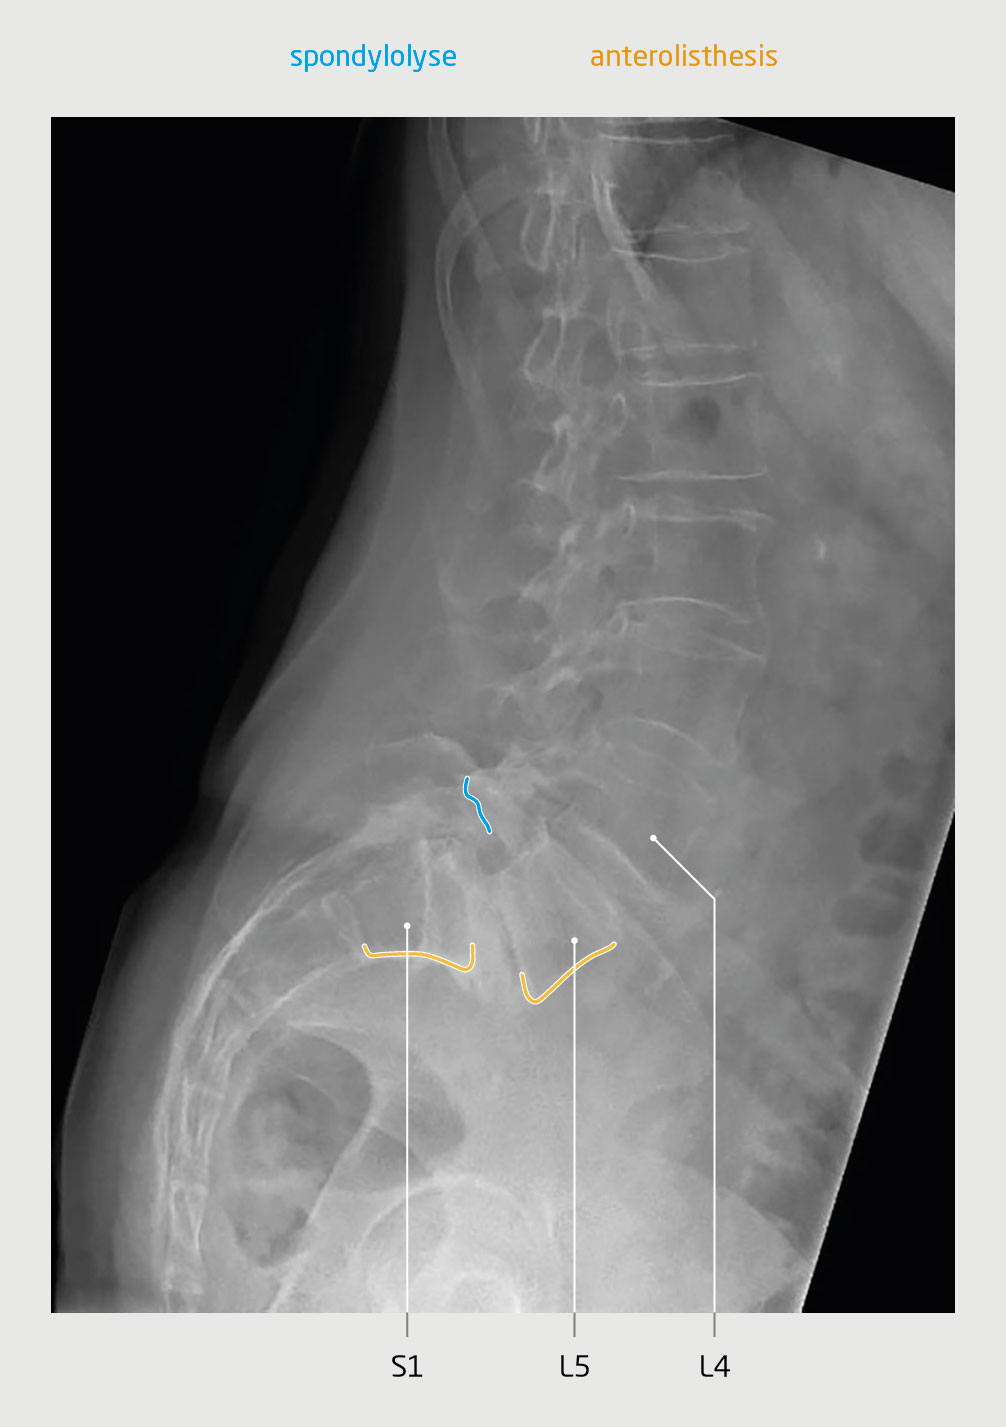

Bij het lichamelijk onderzoek vonden wij geen afwijkingen. De röntgenfoto en de MRI-scan van de lumbale wervelkolom toonden een defect in de wervelboog ter plaatse van de pars interarticularis (spondylolyse), wat had geresulteerd in een spondylolisthesis op wervelniveau L5-S1 (figuur 1), met een foramenstenose en compressie van de zenuwwortel L5 rechts (zie ook de video).

Figuur 1 | Lytische spondylolisthesis

Sagittale röntgenfoto van de lumbale wervelkolom van patiënt A toont een defect in de wervelboog ter plaatse van de pars interarticularis (spondylolyse), met als gevolg spondylolisthesis (anterolisthesis) op wervelniveau L5-S1.